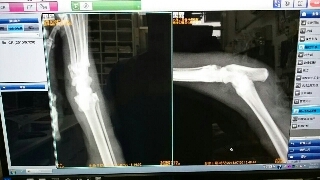

經醫生檢查發現內外都有傷口,懷疑是狗咬住拉扯,韌帶有斷裂,導致關節不穩定。

傷口因咬傷已數日,內部感染嚴重且肌肉已壞死。韌帶有撕裂,造成關節有骨摩擦音。但還好X光並無發現骨折。